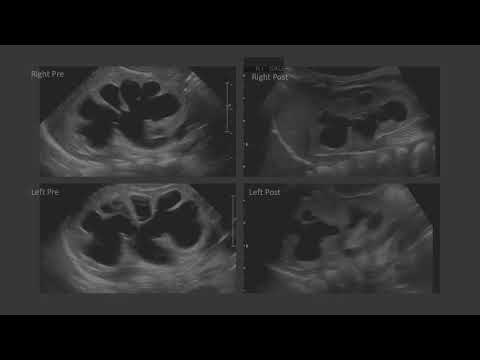

Re-implantation surgery: When and How?, by professor Waleed Dawood